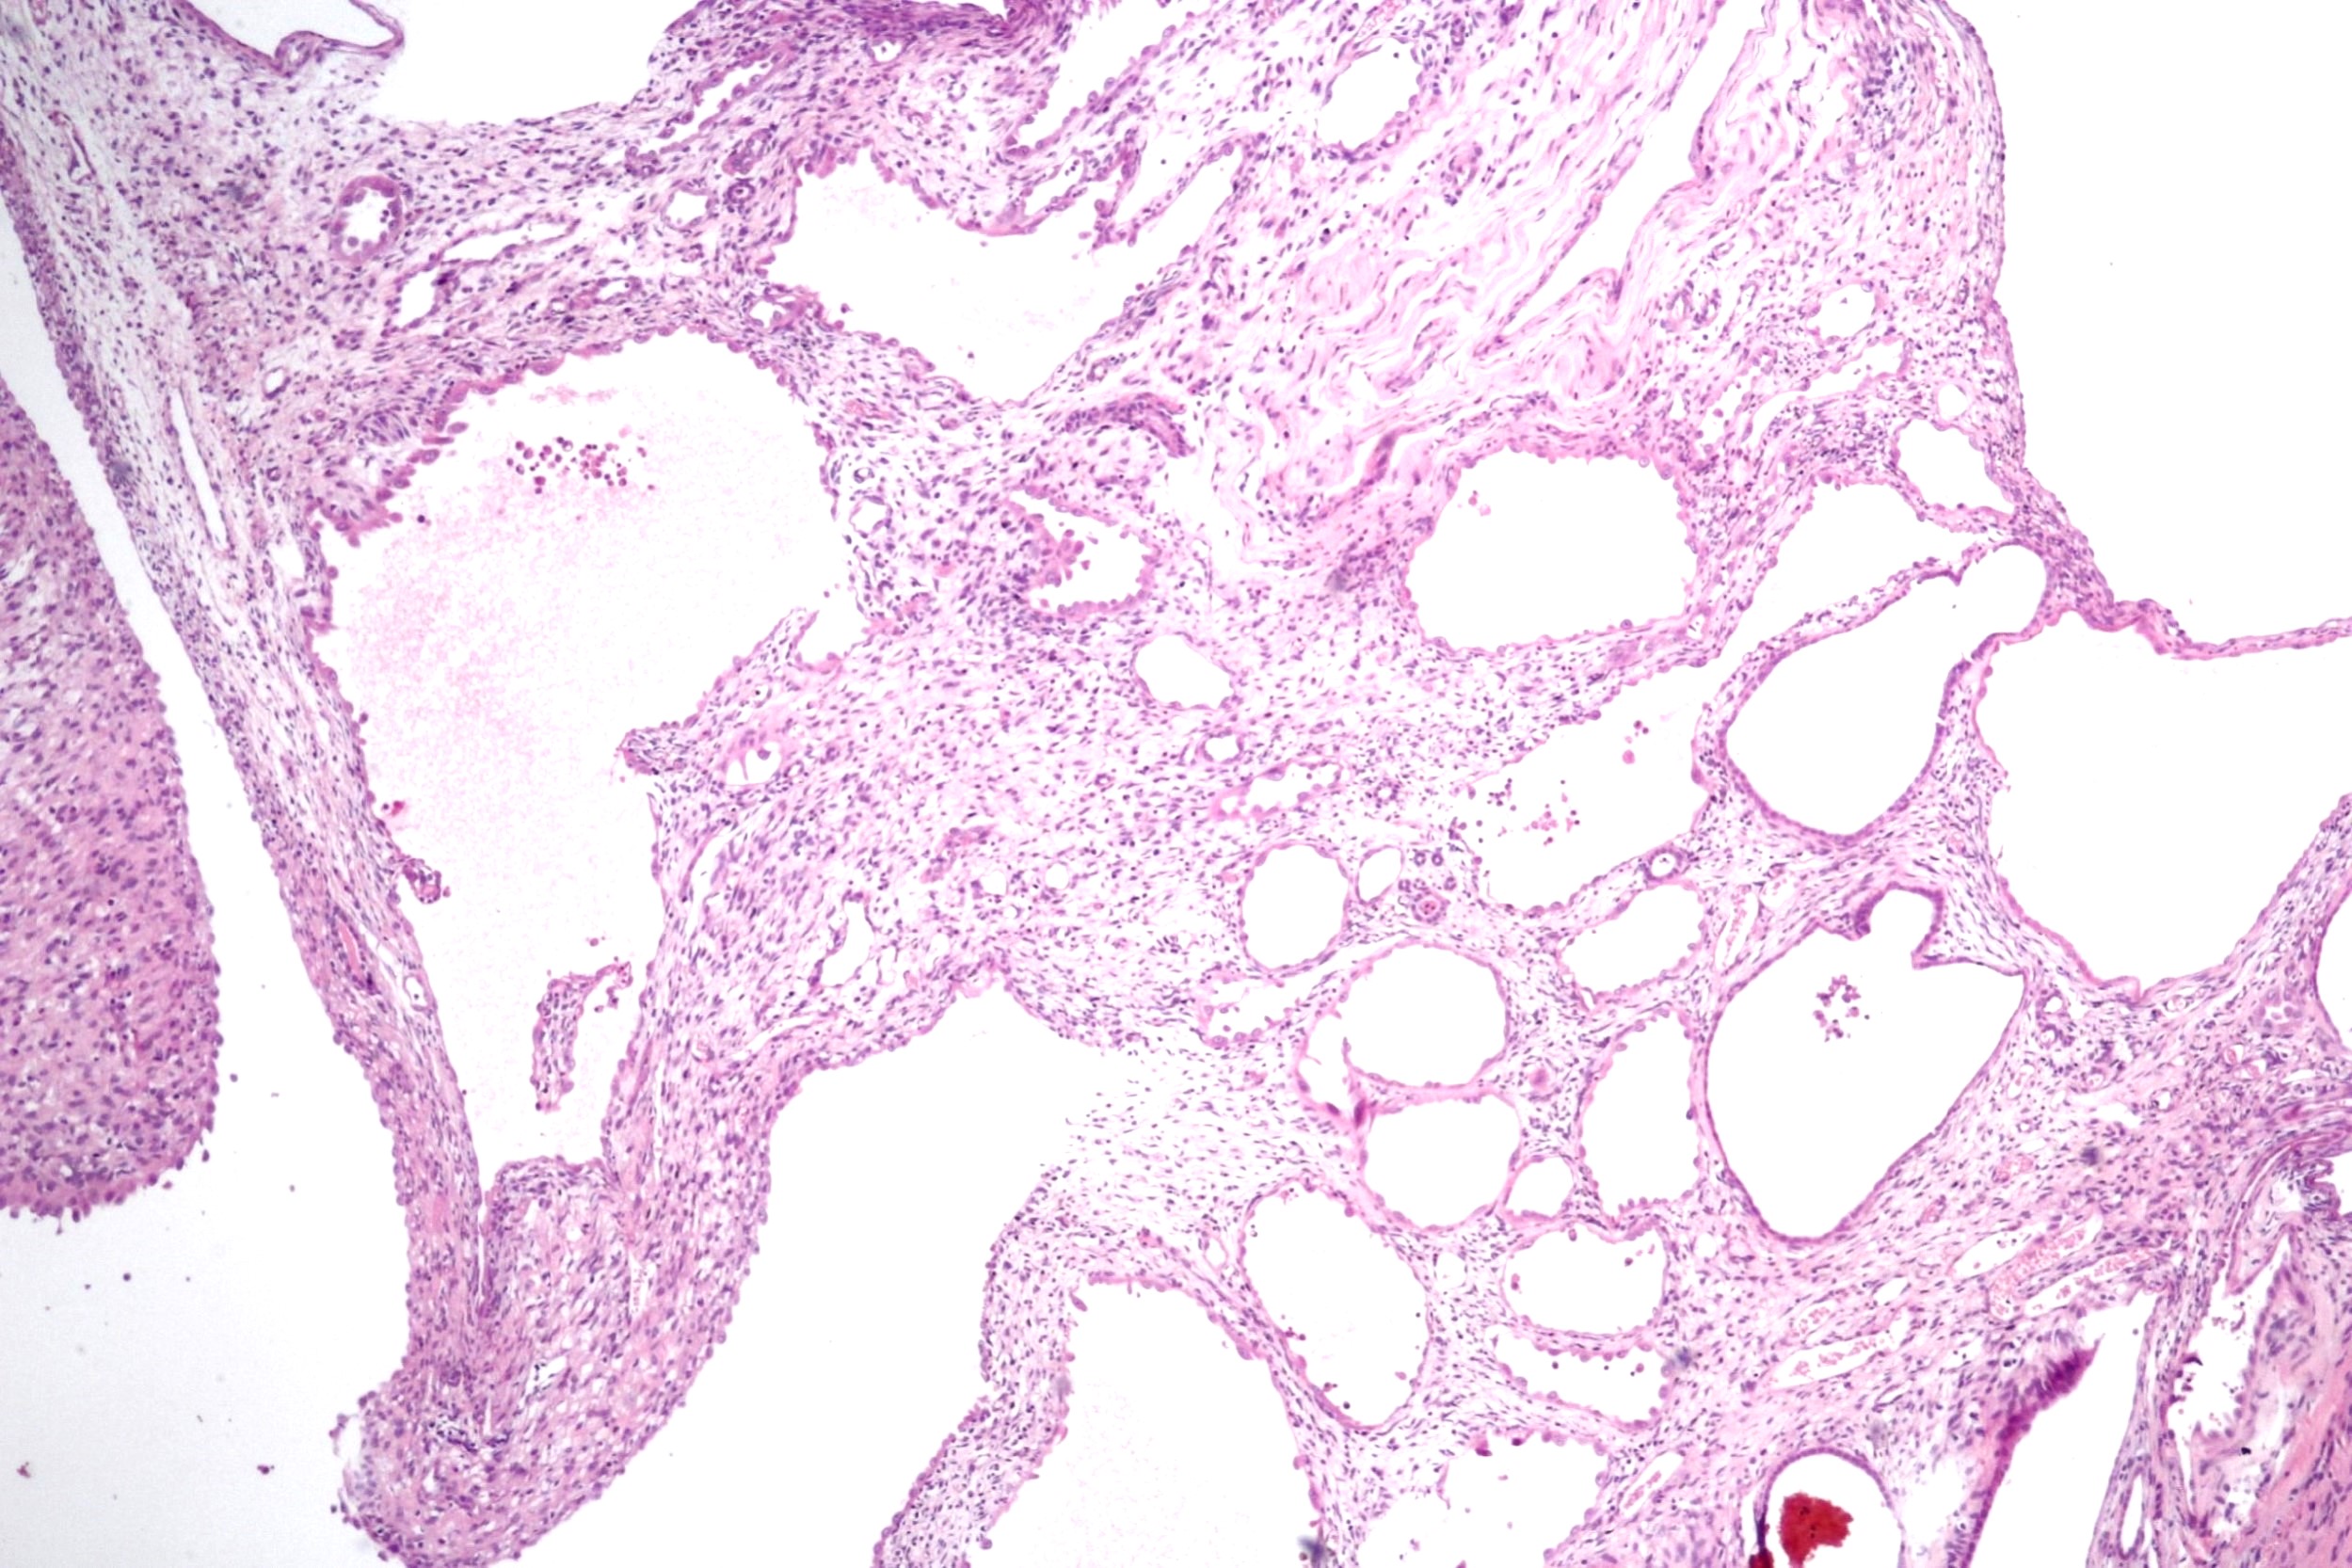

Microscopic (histologic) description

- Cysts lined with flat / cuboidal / hobnail cells (or are denuded)

- Epithelial elements consist mainly of mature and immature / abortive tubules and small papillae resembling immature glomeruli

- Key histological findings of the variably cellular septa include

- Nephroblastomatous epithelial elements

- Islands of undifferentiated blastema and differentiated mesenchymal elements (skeletal muscle and less often cartilage and fat) (J Urol 2010;183:1585)

- Focally, the septal elements may protrude into the cystic spaces in microscopic papillary folds

Microscopic (histologic) images

Contributed by Americo Brilhante, M.D. and Daniel Athanazio, M.D., Ph.D.